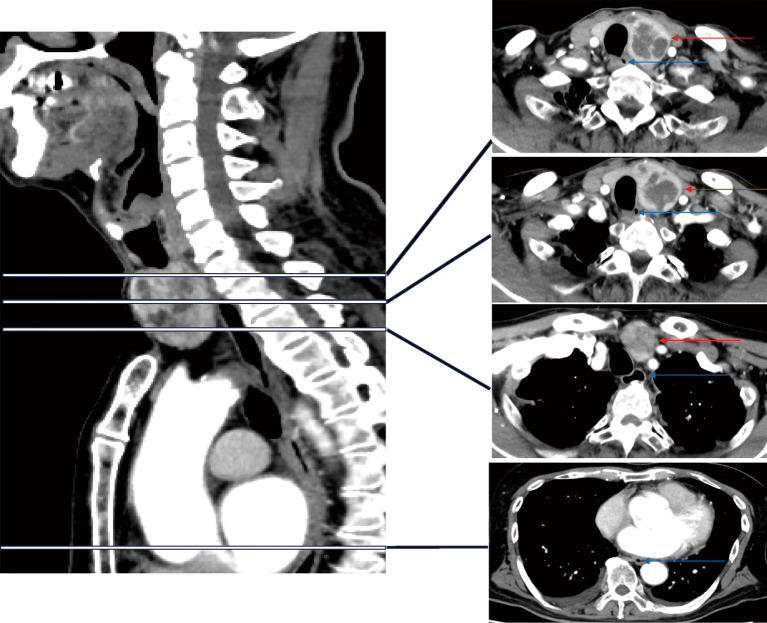

Case description: A 78-year-old man (170 cm, 68 kg) with severe mitral regurgitation (MR) was scheduled for simultaneous thyroid surgery and MVP, since preoperatively, experienced cardiologists had failed to place an adult TEE probe for preoperative TEE examinations, and they had had to use a pediatric TEE probe with poor image quality. First, otolaryngologists completely resected the left thyroid lobe including goiter. However, even after tumor resection, experienced anesthesiologists could not advance the adult TEE probe beyond the pharynx due to strong resistance, even using video laryngoscopy to visualize the esophageal inlet. Again, they had to use a pediatric probe for intraoperative evaluation.

Conclusions: Such previously unreported experiences suggested that esophageal stenosis due to chronic compression by goiter would not improve completely at least immediately after tumor resection. When usual TEE probe placement is difficult, alternative methods for assessing the mitral valve (MV) should be considered.